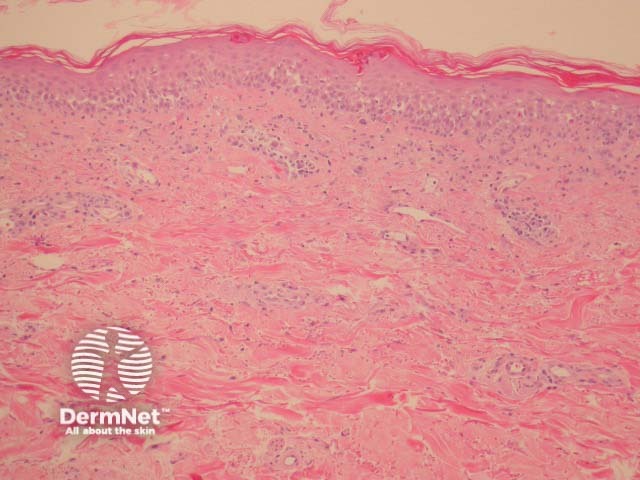

In paraneoplastic pemphigus, there is usually an overt interface or lichenoid infiltrate associated with necrotic keratinocytes at all levels of the epidermis (figures 1-3) to resemble erythema multiforme. In addition, foci of suprabasal acantholysis are seen. Sometimes the acantholysis can be very difficult to find making diagnosis difficult.

Direct immunofluorescence usually shows intercellular and basement membrane deposition of IgG and C3.

The features histologically resemble lichenoid eruptions (such as erythema multiforme, lichen planus, drug eruptions), and other immunobullous diseases (pemphigus vulgaris). Correlation with the clinical findings and immunofluorescence is invaluable in arriving at the correct diagnosis.